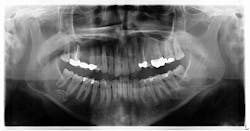

Radiographic assessment revealed a radiopaque s-/oval-shaped lesion on the right side of the mandible just inferior to the apical roots of tooth no. 31 (figure 1). The patient reported no sensitivities or tenderness in the area and was unaware of any potential pathology. Previous panoramic radiographs were not obtainable. At that time, we explained to the patient that we would reexamine the lesion with a subsequent radiograph in the next year to assess for any changes.